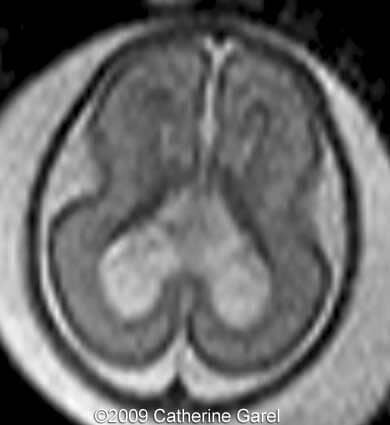

Images 7,8: MRI Image 7 shows a wavy midline structure which was detected on the ultrasound images (Images 4,6), the structure is hypodense on the MRI images. Image 8 shows an interhemispheric fissure in the anterior and posterior region.

Case262_7

Case262_8

Images 9,10: Images 9, 10 show a fusion in the posterior frontal and parietal regions, indicated by arrows.

Case262_9a

Case262_10a